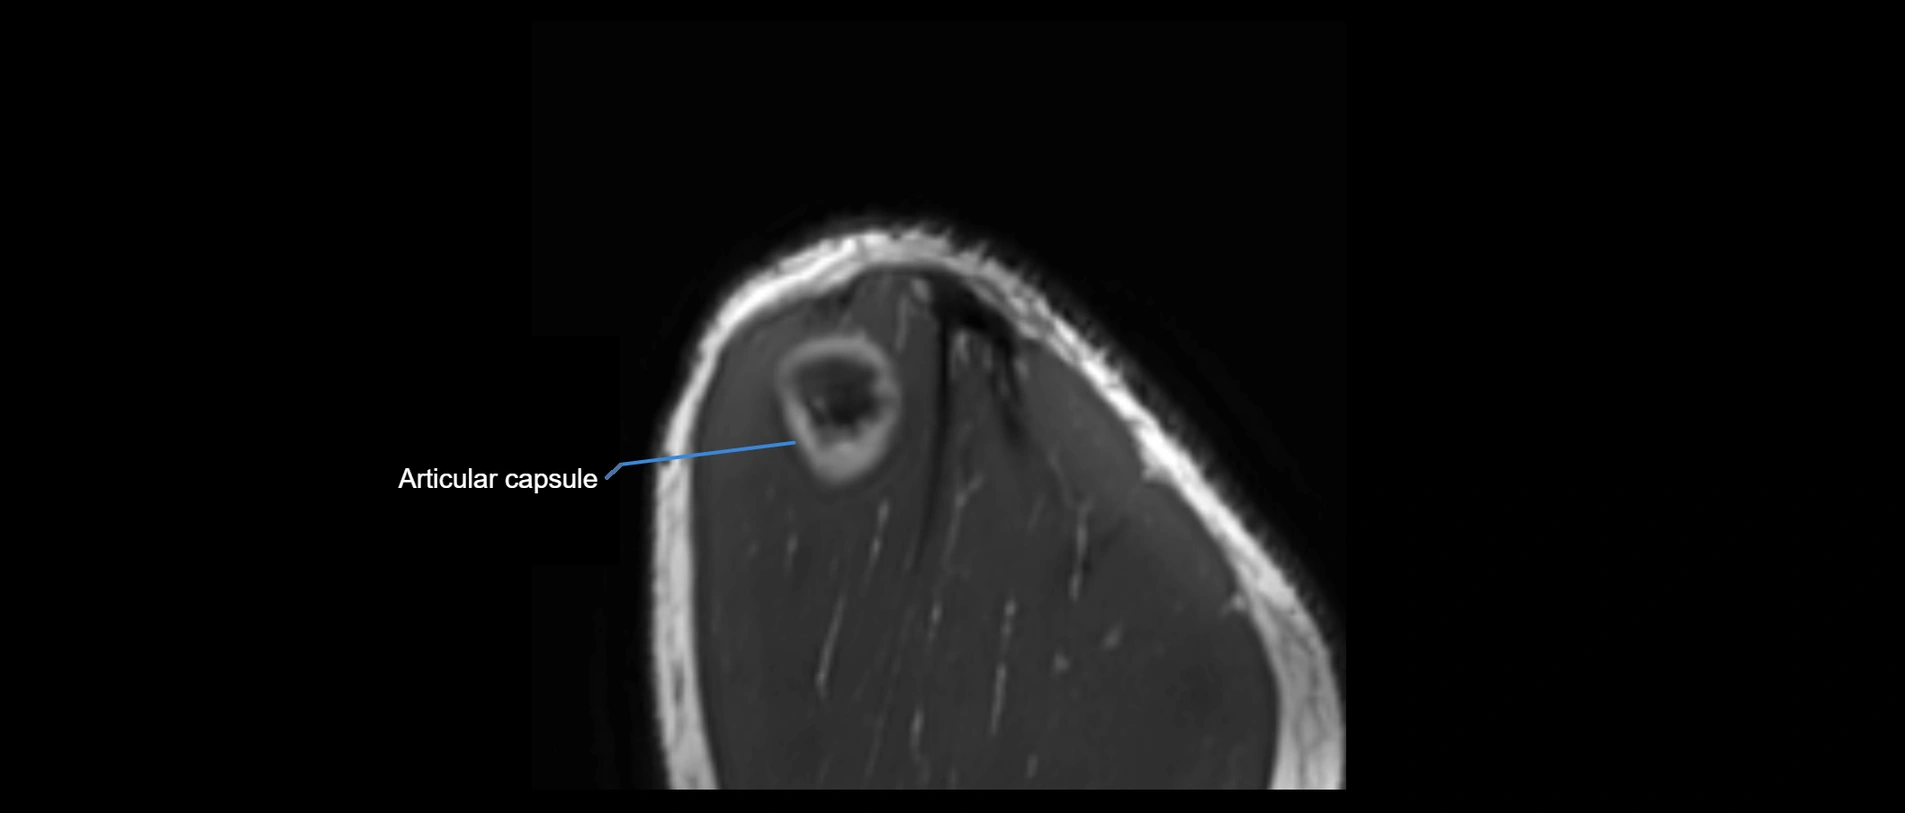

MRI images

image